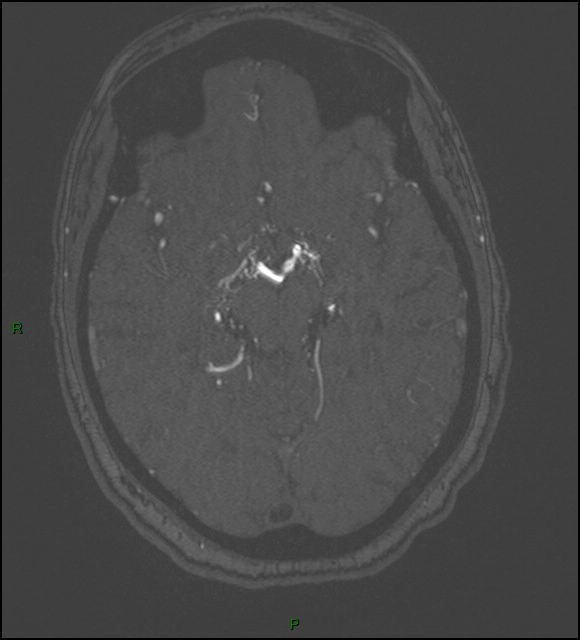

Bệnh Moyamoya (Moyamoya disease)

16/03/2026